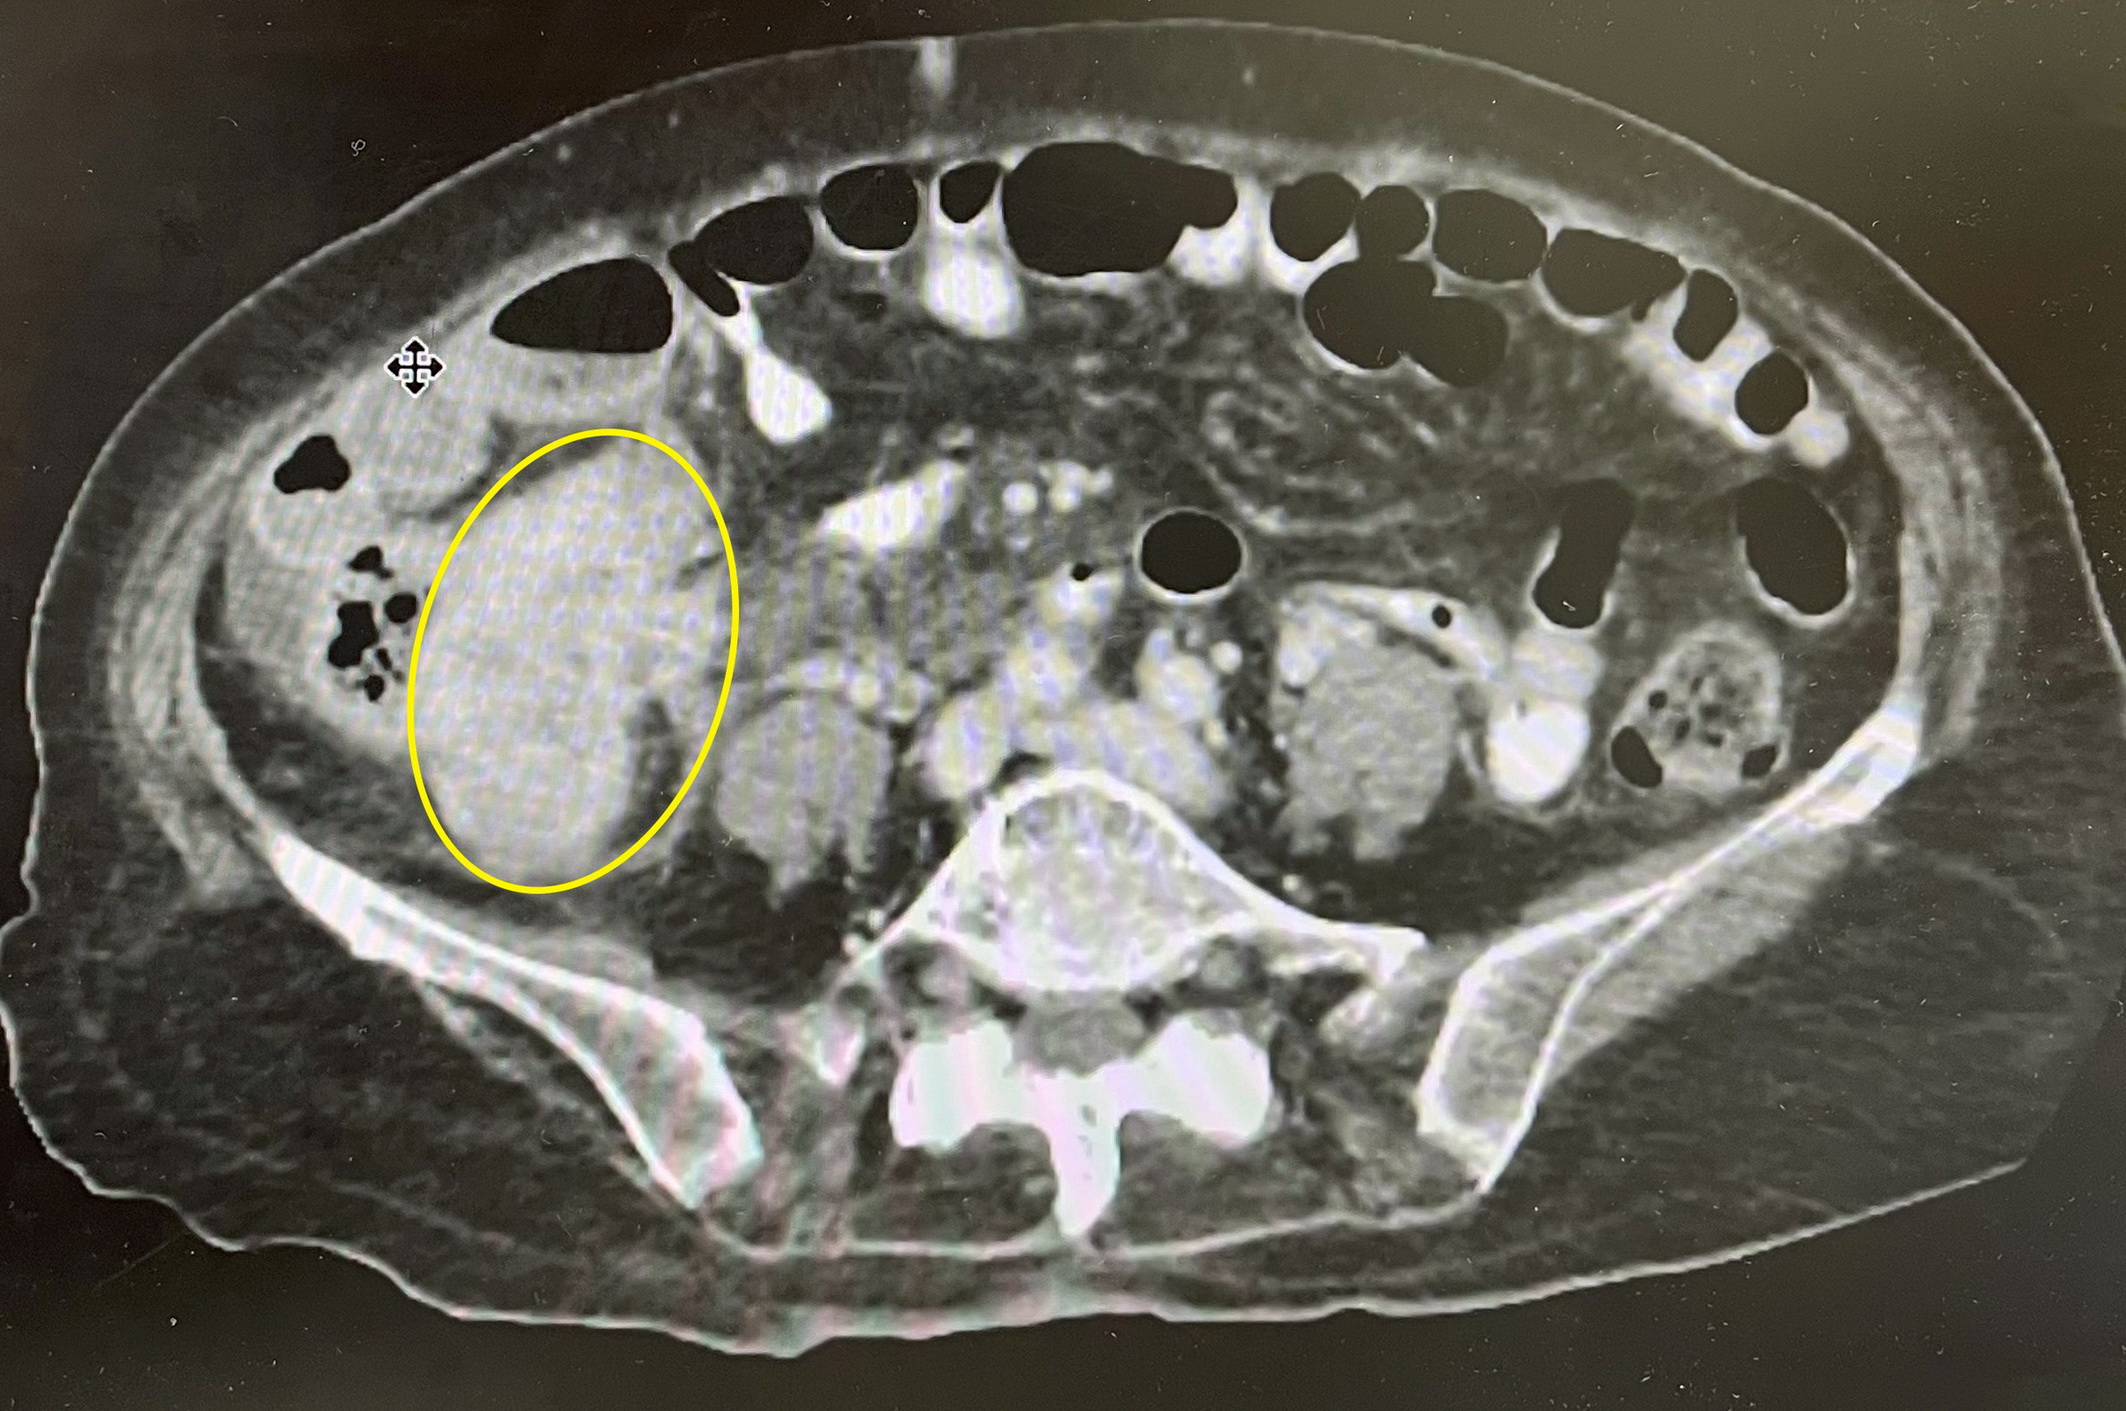

老婦人平常身體無異狀,只是幾個月來覺得右下腹隱隱作痛,能忍就忍,不想給子女帶來麻煩,直到最近真的痛到無法走路,才由兒子陪同看了胃腸肝膽科門診,抽血檢查血紅素掉到8.7(正常12至16)、白血球15900(正常10000以下),再經腹部電腦斷層檢查,發現右下腹部有一大團約10公分大腫瘤,外形呈不規則狀,診斷是大腸癌並已破裂,收治住院緊急會診大腸直腸外科。

陳周誠表示,經手術發現該老婦人右側大腸腫瘤約5.6公分大,腫瘤鑿穿大腸壁,溢出腫瘤物形成約4.9公分大破裂範圍,侵犯到迴腸末段,經手術切除大腸癌患部5公分,受癌細胞侵犯的迴腸55公分,再將小腸和大腸精密吻合,築出一新的通道,維持腸道的暢通。